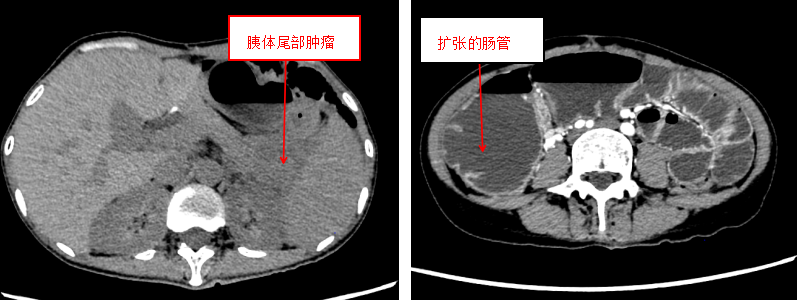

时间拉回两年前,王女士因胃癌在外院接受全胃切除+食管空肠吻合术,术后坚持完成 12 次全身化疗,本以为能逐步恢复正常生活,命运却再次给她沉重一击。半年前,PET 检查显示胰腺体尾部出现肿物,家人带着她连夜赶赴北京,先后求诊于多家知名医院,得到的却是一致的坏消息:「患者营养状况差、基础条件弱,无法耐受复杂手术,建议保守治疗。」

「患者入院时情况极差,不仅有胰腺尾部 8 cm 肿瘤侵犯脾脏,还有食管空肠吻合口梗阻、结肠脾区肿瘤导致的全消化道闭襻梗阻,相当于整个消化道『堵死了』,再不干预随时可能出现肠穿孔、感染性休克。」李森主任回忆起初次会诊的场景,仍不由皱紧眉头。

导管置入术后 3 天,患者腹痛明显缓解,能少量进食流质食物,体重也略有回升。此时结肠镜检查进一步明确:结肠脾区存在直径约 10 cm 的肿瘤,正是导致结肠梗阻的「元凶」。「时机成熟了,可以手术!」李森主任斩钉截铁地说。